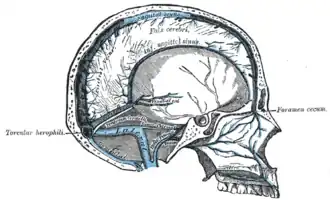

Sagittal section of the skull, showing the sinuses of the dura. (Labeled with "torcula herophili".) | |

The confluence of sinuses (Latin: confluens sinuum), torcular Herophili, or torcula is the connecting point of the superior sagittal sinus, straight sinus, and occipital sinus. It is below the internal occipital protuberance of the skull. It drains venous blood from the brain into the transverse sinuses. It may be affected by arteriovenous fistulas, a thrombus, major trauma, or surgical damage, and may be imaged with many radiology techniques.

Structure

The confluence of sinuses is found deep to the internal occipital protuberance of the occipital bone of the skull.[1] This puts it inferior to the occipital lobes of the brain, and posterosuperior to the cerebellum.[1] It connects the ends of the superior sagittal sinus, the straight sinus, and the occipital sinus.[1] Blood from it can drain into the left and right transverse sinuses.[1] It is lined with endothelium, with some smooth muscle.[1]

The confluence of sinuses may also be known as the confluens sinuum (from Latin), or the torcular Herophili (or more simply the torcula). The last term is older, and describes the veins as a gutter or canal. This is named after Herophilos, the Greek anatomist who first used cadavers for the systematic study of anatomy. This term more precisely refers to the concavity in the bone, which is the location of the confluence of sinuses.[4]